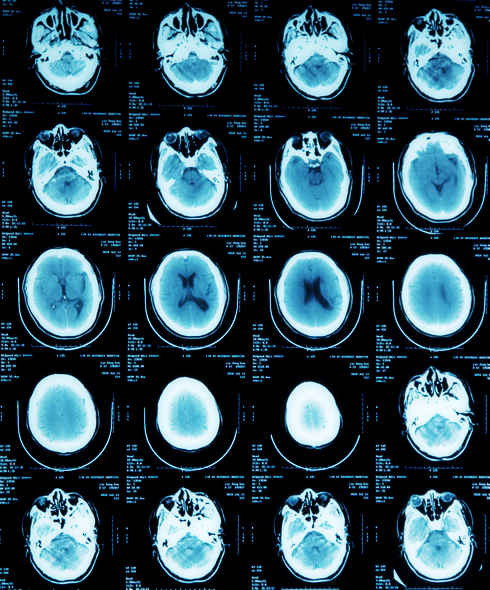

患者金某某,男,58岁,主因反复头晕2年,加重伴左侧肢体麻木1年入院。患者2年前无明显诱因突然出现头晕,伴左侧肢体力弱,无明显头痛、恶心。呕吐,无视物旋转、耳鸣、听力下降、黑曚、晕厥、肢体抽搐,于当地医院行头颅CT检查示双侧多发腔隙性脑梗塞。给予改善脑循环、降压等药物治疗(具体不详)后症状好转。1年前无诱因再发头晕不适,伴左侧肢体麻木,偶有黑曚出现,无肢体力弱、耳鸣、视物旋转。于当地医院保守治疗后好转。住院期间行造影提示左侧颈内动脉狭窄。为进一步治疗入住北京市第六医院。

颈动脉超声:双侧颈动脉粥样硬化斑块形成;双侧颈内静脉未见明显异常。